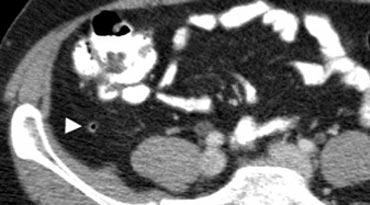

Hình 2. Nam giới 50 tuổi với ruột thừa bình thường. CT không tiêm thuốc cản quang cho thấy ruột thừa chứa khí, không giãn (đầu mũi tên) với mô mỡ quanh ruột thừa đồng nhất, không có dấu hiệu thâm nhiễm mỡ.